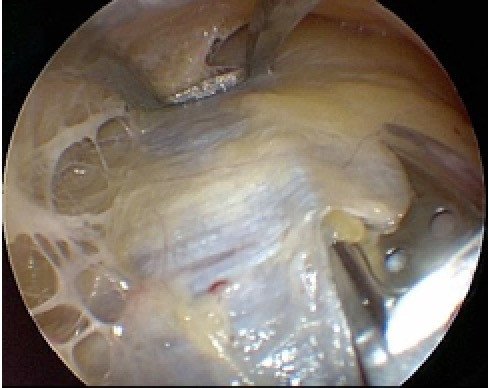

Bei der Operation werden über zwei kleine Inzisionen direkt über den betreffenden Muskellogen am Unterschenkel kniegelenksnah eine Kamera sowie eine Spezialklinge eingeführt, um die gespannte Abgrenzung der Loge, die Unterschenkelfaszie, nahezu in ihrer gesamten Länge unter Sicht zu spalten.